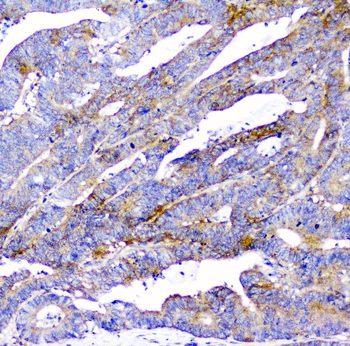

100 μg, 10 μg - Anti-Glucose Transporter GLUT1/SLC2A1 Antibody [orb259612]

FC, ICC, IF, IHC, IHC-Fr, WB

Human, Mouse, Rat

Rabbit

Polyclonal

Unconjugated